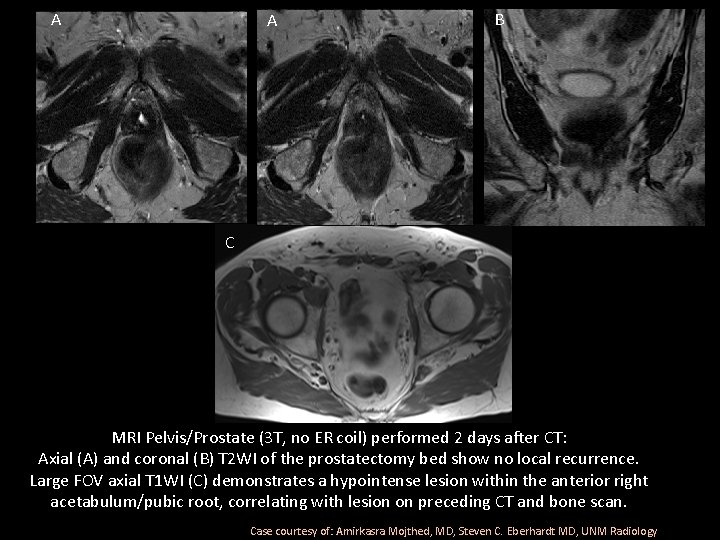

A B C MRI Pelvis/Prostate (3 T, no ER coil) performed 2 days after CT: Axial (A) and coronal (B) T 2 WI of the prostatectomy bed show no local recurrence. Large FOV axial T 1 WI (C) demonstrates a hypointense lesion within the anterior right acetabulum/pubic root, correlating with lesion on preceding CT and bone scan. Case courtesy of: Amirkasra Mojthed, MD, Steven C. Eberhardt MD, UNM Radiology